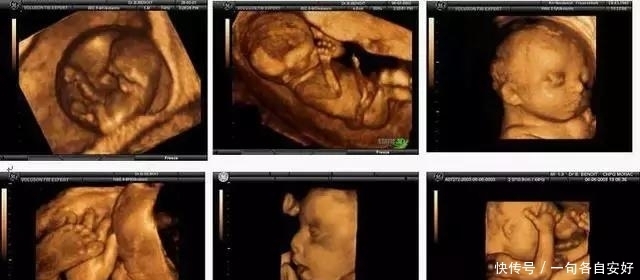

普通B超、彩超和三维、四维彩超有什么区别?

可以这样理解,普通B超就像黑白照片,而彩色B超就像彩色照片,三维B超就像是立体彩色照片,四维B超则像是摄像机所拍摄的VCR。

普通B超和彩色B超看到的都只是一个平面,而三维和四维B超看到的是胎儿的立体图像。而三维和四维的区别呢?仅仅就在于一个“时间维”。通俗的来说,三维就好比是图片,而四维就好比是录像。三维是静态的,而四维却是动态的,可以看到宝宝一连串的动作。